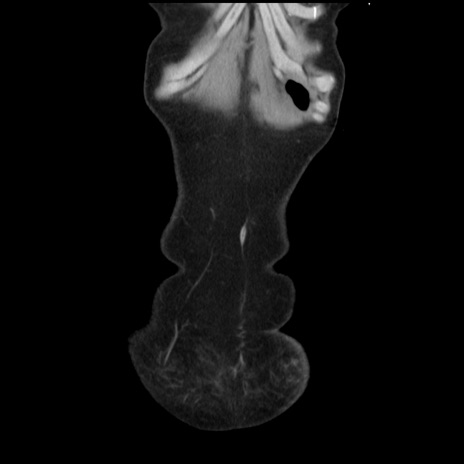

矢状断像

【症例】40歳代 女性

【主訴】上腹部痛、嘔気・嘔吐

【現病歴】約9時間前頃から急に上腹部痛、嘔気、嘔吐が出現。改善しないため救急要請。

【既往歴】子宮頚癌(広汎子宮全摘術、放射線療法)、腸閉塞

【身体所見】腹部:平坦、軟、腸雑音亢進、上腹部を中心に腹部全体に圧痛あり。

【データ】WBC 8400、CRP 0.03